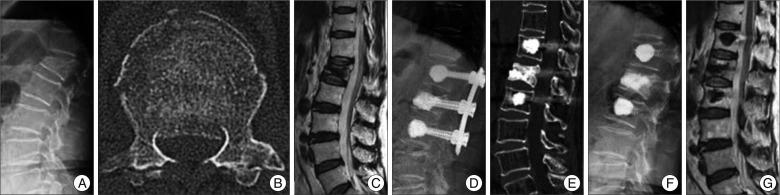

Sixteen patients with a single-level thoracolumbar burst fracture (T11-L2) accompanying severe osteoporosis treated from January 2008 to November 2009 were prospectively analyzed. Surgical procedures included postural reduction for 3 days and bone cement augmented percutaneous screw fixation at the fracture level and at adjacent levels without bone fusion. Due to the possibility of implant failure, patients underwent implant removal 12 months after screw fixation. Imaging and clinical findings, including involved vertebral levels, local kyphosis, canal encroachment, and complications were analyzed.

Prior to surgery, mean pain score (visual analogue scale) was 8.2 and this decreased to a mean of 2.2 at 12 months after screw fixation. None of the patients complained of pain worsening during the 6 months following implant removal. The percentage of canal compromise at the fractured level improved from a mean of 41.0% to 18.4% at 12 months after surgery. Mean kyphotic angle was improved significantly from 19.8° before surgery to 7.8 at 12 months after screw fixation. Canal compromise and kyphotic angle improvements were maintained at 6 months after implant removal. No significant neurological deterioration or complications occurred after screw removal in any patient.

Bone cement augmented short segment fixation using a percutaneous system can be an alternative to the traditional open technique for the management of selected thoracolumbar burst fractures accompanied by severe osteoporosis.